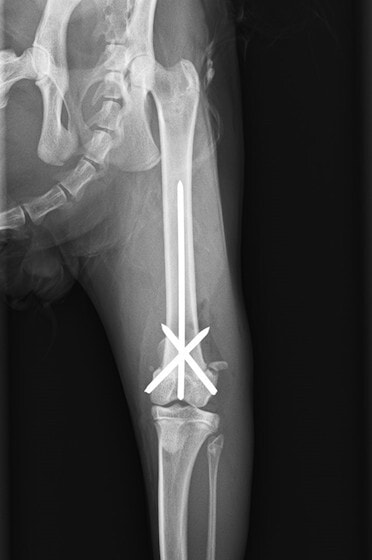

症例3:キルシュナーワイヤーのピンニングによる整復

ペルシャ猫 11ヶ月齢 雄

他院にて左大腿骨遠位の成長板骨折(salter-harrisⅠ型)が認められており、治療相談を目的として来院。当院にて、キルシュナーワイヤーを用いたピンニングにより骨折部位の整復を行いました。術後の経過は良好で、現在も経過観察中です。

術前レントゲン

術後レントゲン

機器

Arthrex社のターゲティングデバイスを用いてピンニングの位置を調整することで、確実な固定を行っています。当院ではこの手術器具以外にも、人の手術にも使用される様々な器具を導入し、手術精度を高め、また医療メーカーと新しい器具の開発、試作にも取り組んでおります。